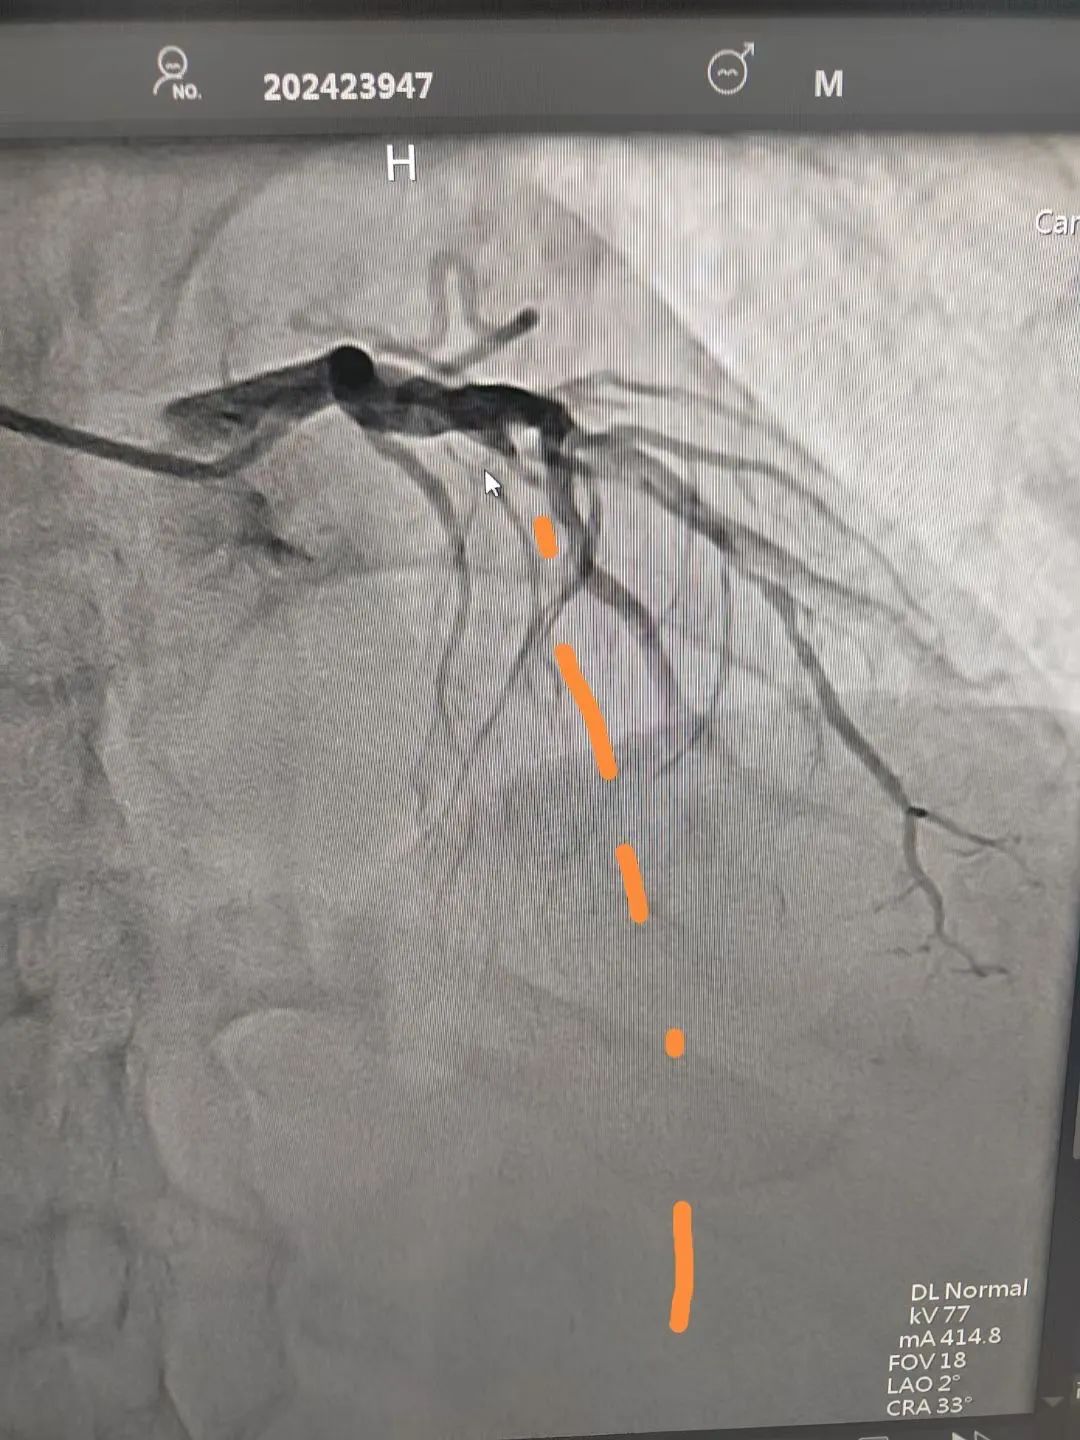

图为造影提示:第一钝缘支次全闭塞。